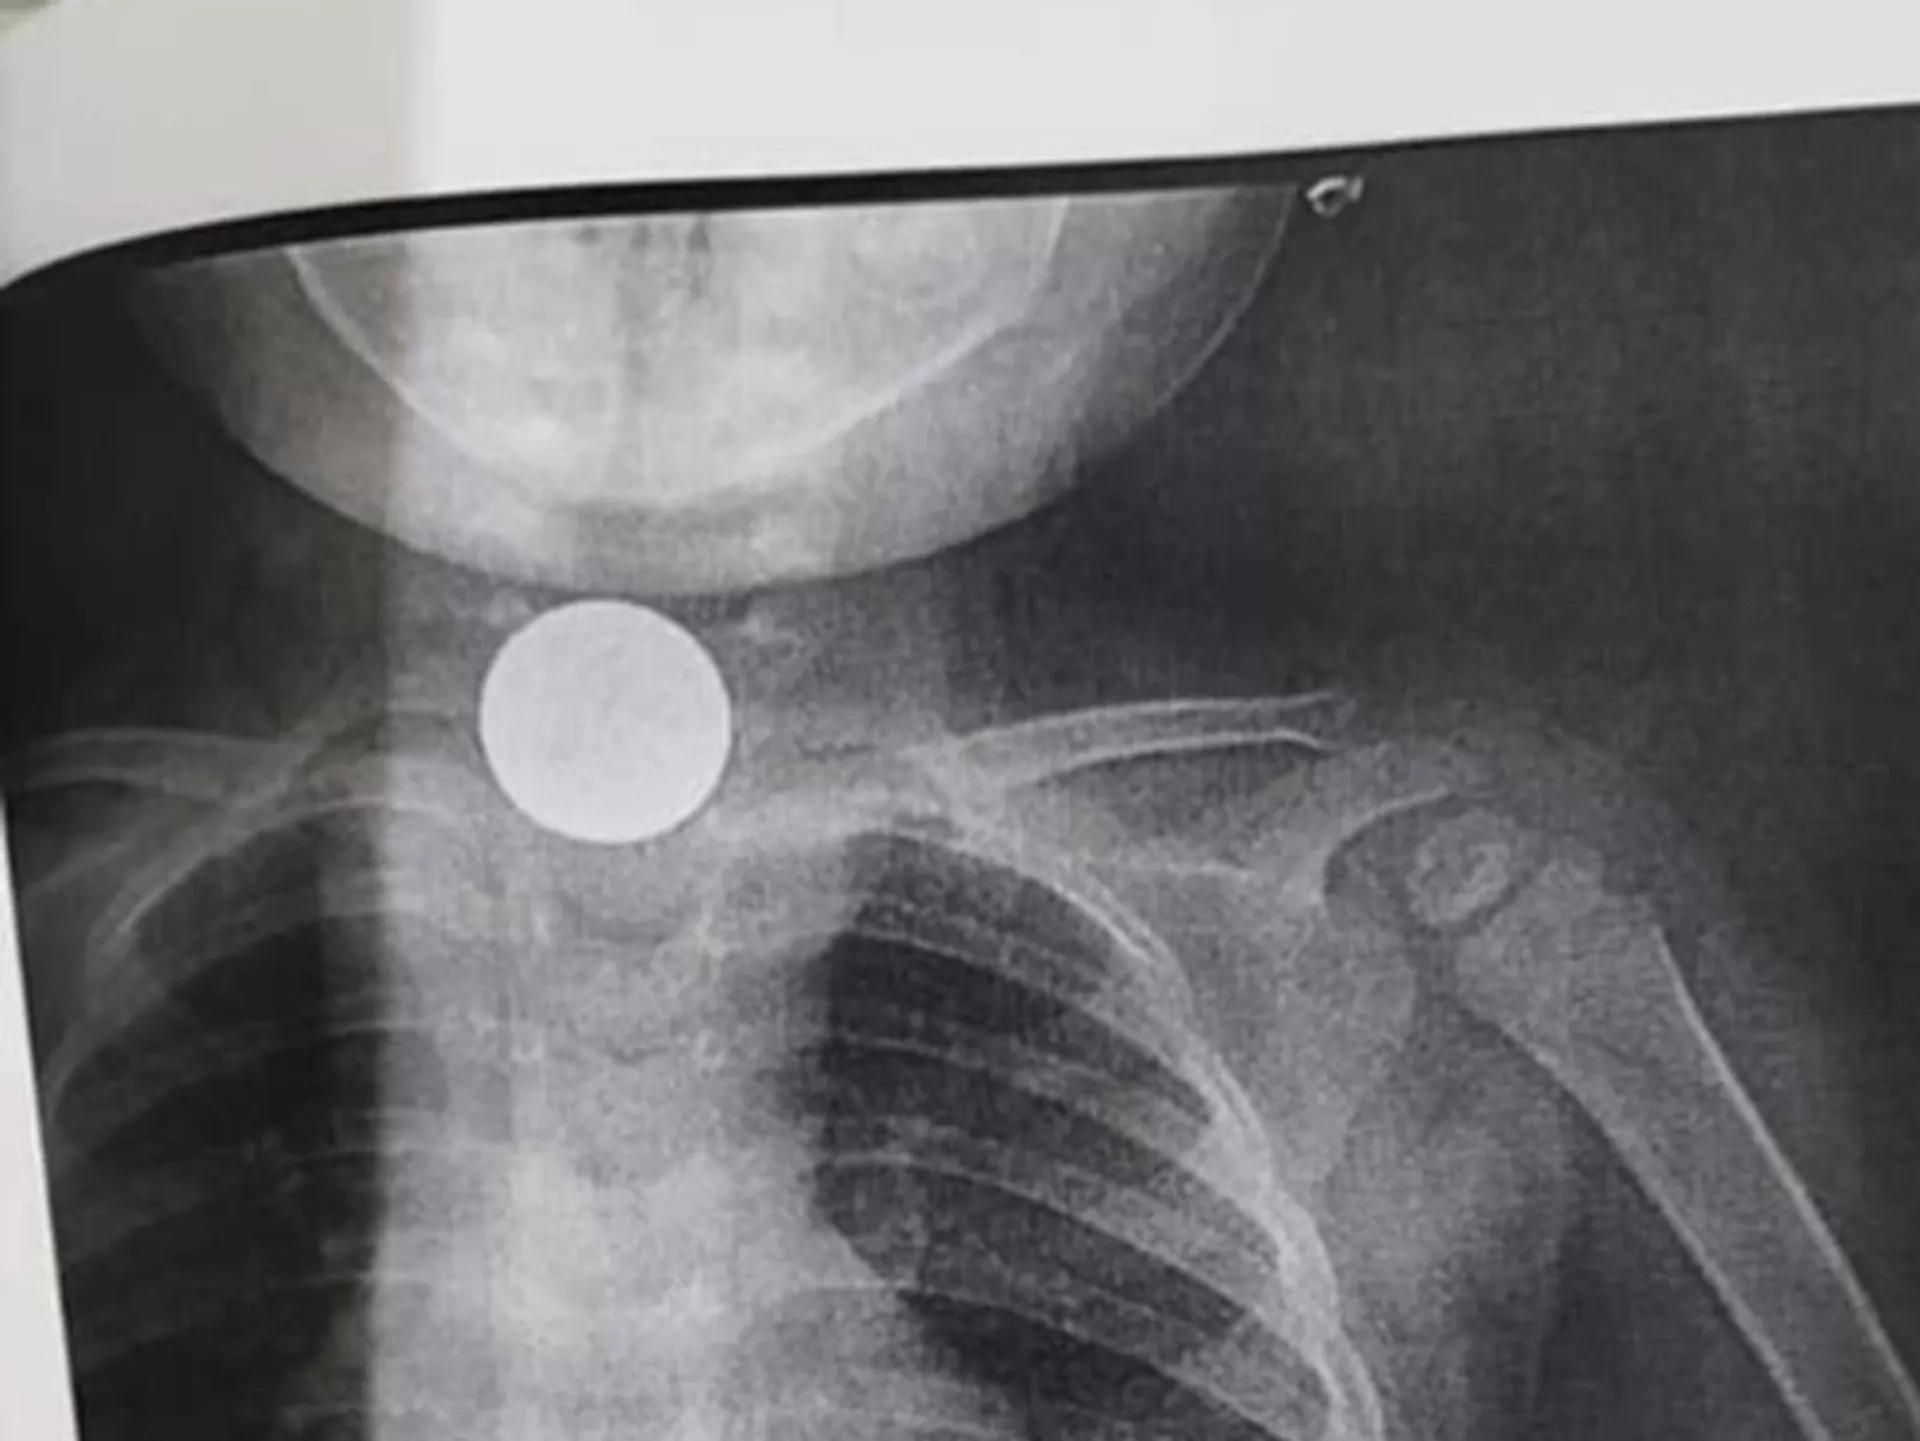

В Оше двухлетняя девочка проглотила монету — предмет 2 месяца был в ее пищеводе

© Фото / Ошская межобластная детская клиническая больницаДвухлетняя девочка проглотила монету в Оше

БИШКЕК, 11 сен — Sputnik. В Оше двухлетняя девочка проглотила монету. Посторонний предмет два месяца был в ее пищеводе. Об этом сообщает Ошская межобластная детская клиническая больница.

Предположительно, это монета номиналом 5 сомов.

В Оше двухлетняя девочка проглотила монету